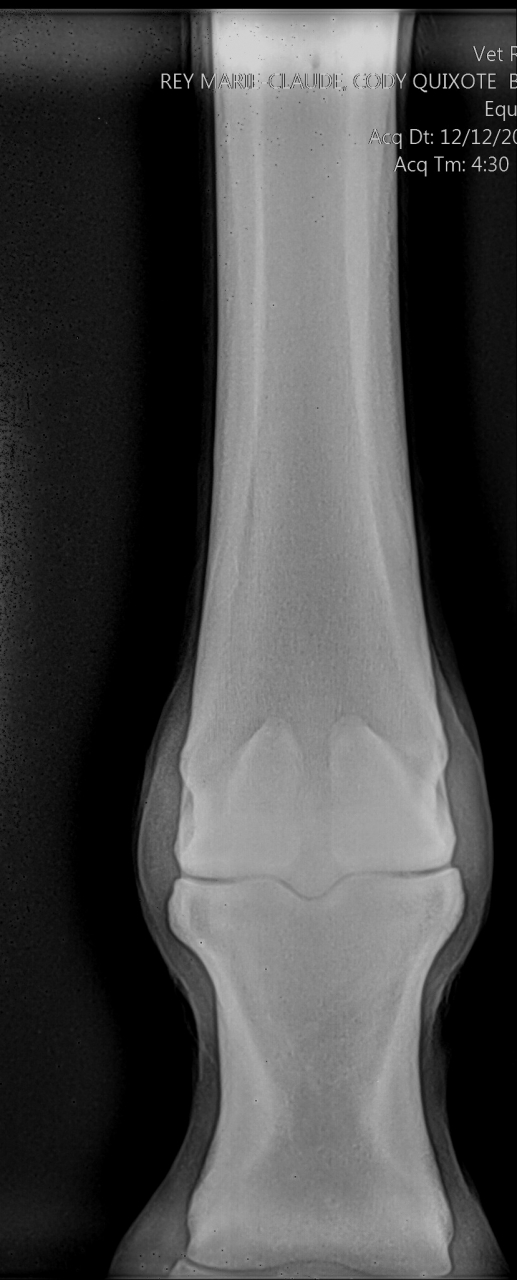

| Dire merci | Voici le compte-rendu du véto : Examen général: L’examen locomoteur au pas et au trot en ligne droite ne met pas en évidence de boiterie. Le cheval pose l’antérieur droit en deux temps : pose d’abord en muraille externe puis en interne. Une boiterie 2/5 de l’antérieur gauche apparait sur le cercle au trot à droite Examens complémentaires : Radiographie : Pieds de face : 3-4 fossettes synoviales sur le bord distal du naviculaire antérieur droit, de profondeur faibles et peu ouvertes. 2-3 fossettes synoviales dont l’une plus ouverte sur le bord distal du naviculaire antérieur gauche Léger pincement articulaire p1-p2 et p2-p3 coté externe visible sur le membre à l’appui. Boulet de face : Petit remaniement osseux au niveau de l’insertion proximale du ligt coll int Boulet et pieds ant droit de profil : ras La boiterie étant trop légère pour préciser la localisation par anesthésie étagée, plusieurs hypothèses sont envisagées. Par ordre d’importance : • Pincement et fatigue articulaire lié au parage ou à une compensation d’une légère entorse boulet • Entorse du boulet • Début syndrome podotrochléaire Message édité le 14/05/19 à 18:37 |